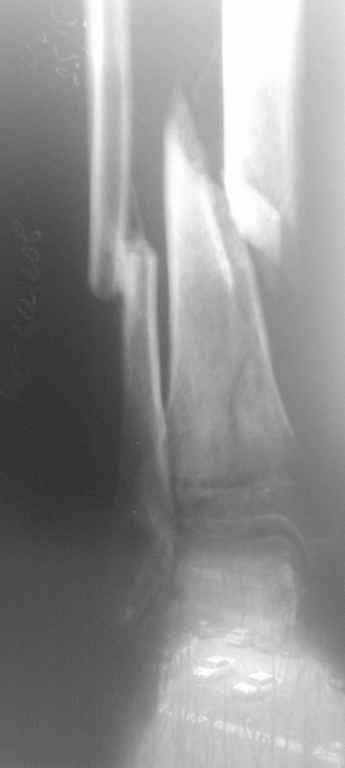

Д\з Неправильно консолидированный перелом м\берцовой кости, ложный сустав(учитывая подвижность в области перелома) б\берцовой кости правой голени. Остеопороз костей правой голени, стопы. Постиммобиллизационные контрактуры коленного, голеностопного суставов.

Больной Б. травма в августе месяце 2010г., находился на СВ, отказался от оперативного лечения, со слов больного, не имел средств на приобретение металлоконструкций, СВ вытяжение демонтировано ч\з 3 недели, была наложена циркулярная гипсовая повязка от кончиков пальцев стопы до с\3 бедра, снят 10 ноября, имеется Rg контроль по снятию повязки, первичных и после демонтажа СВ снимков не предоставил, почему не продолжил лечение на СВ, нет сведений.

Сейчас кожные покровы правой голени отёчны, пастозны, умеренно гиперемированны, движения в коленном суставе сгибание 90гр., разгибание 165, голеностопном в пределах качательных. Определяется подвижность в месте перелома. Осевая нагрузка болезненна. На консилиуме решено (учитывая отсутствие возможности наложения аппарата Илизарова) выполнить остеотомию м\берцовой кости остеопериостальную декортикацию б\берцовой кости,репозиция(возможно с укорочением) фиксацию отломков кортикальными винтами, циркляжом с последующим наложением циркулярной гипсовой повязки. Почему не было выполнено при первом поступлении или не доведена репозиция на СВ для меня вопрос. Заранее благодарен.